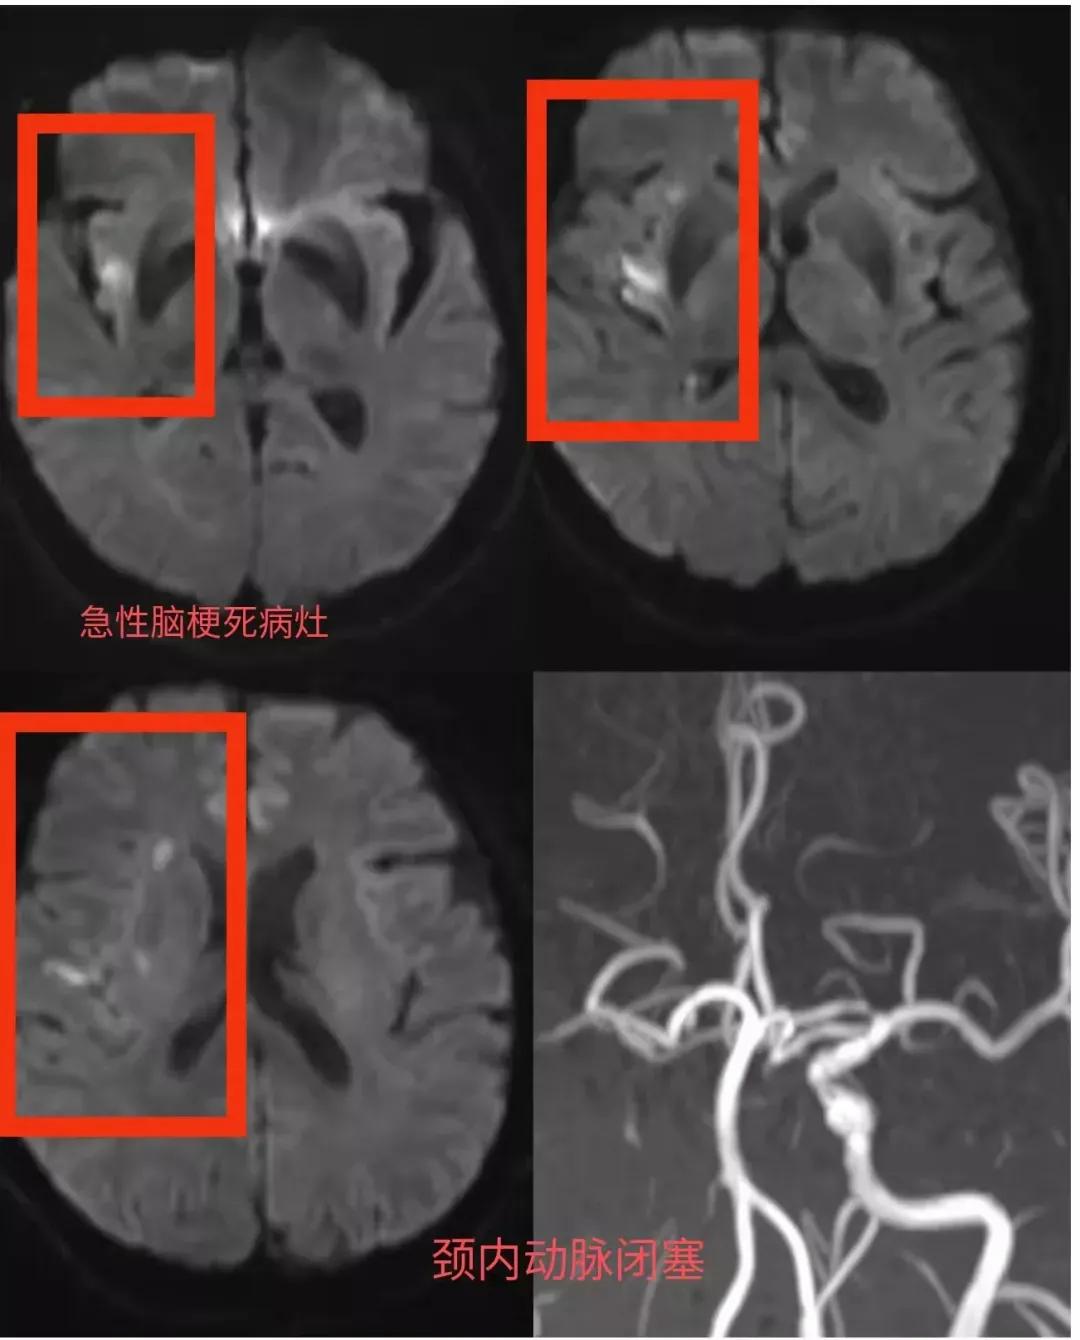

当70多岁的魏大爷被送达医院后,王朝刚医师详细了解了患者的病情,经过完善相关查体,快速进行了CT及磁共振成像检查,诊断魏大爷是:急性脑梗和颈内动脉闭塞。

就在魏大爷家属深深松了口气,以为魏大爷已经转危为安的时候,王朝刚却眉头紧皱,他看着患者的核磁影像学检查,反复跟家属嘱咐道:“魏大爷的病灶虽小,症状轻,但是右侧颈内动脉不显影,整个颈内动脉闭塞,以前的血管情况未知,情况有些复杂,这段时间不能忽视潜在风险,可能随时出现病情加重”。

魏大爷脑血管造影显示:右侧颈内动脉起始处闭塞,王朝刚医师先进行颈内动脉取栓及支架植入术,再通过中间导管在病灶处抽吸出大量暗红色血栓,经过3个多小时的手术,术后魏大爷血管已经完全畅通,下肢肌力也恢复到3级(下肢可以稍微抬起),手术非常成功。